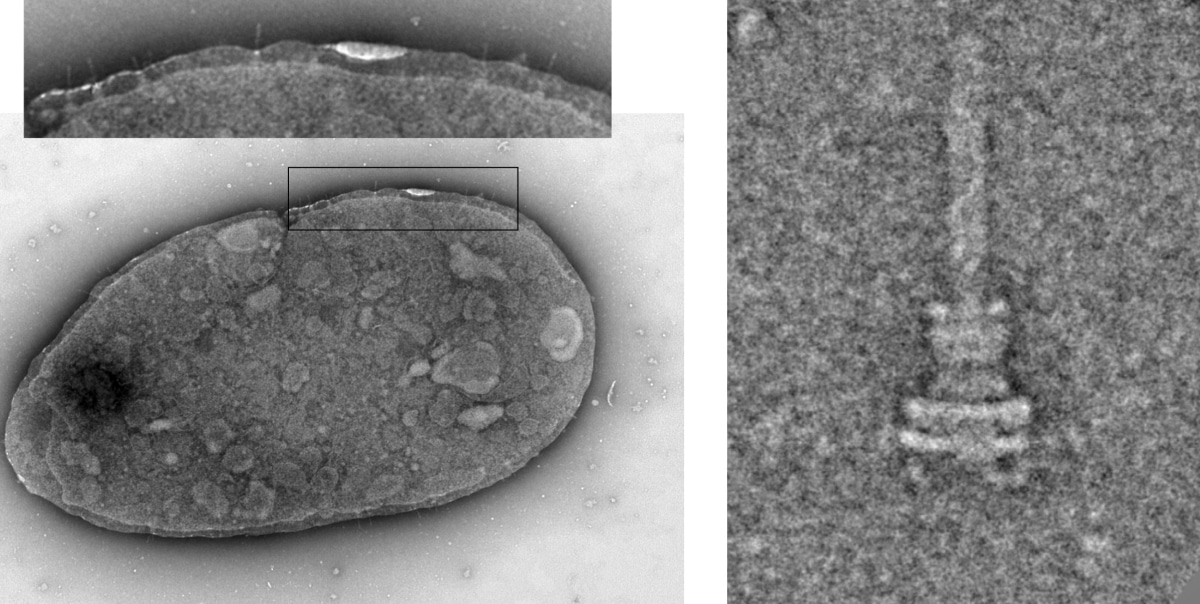

В микробиологии хорошо известна система секреции III типа (T3SS). Это сложный белковый комплекс, который работает как микроскопическая игла со шприцем. Бактерия прокалывает им мембрану клетки хозяина и впрыскивает внутрь свои белки — эффекторы.

Долгое время T3SS считалась атрибутом исключительно опасных патогенов, таких как сальмонелла (Salmonella), чумная палочка (Yersinia) или шигелла. С помощью этого «шприца» они вводят токсины, убивающие клетки. Однако генетический анализ показывал, что гены T3SS встречаются и у безобидных обитателей кишечника, но их функция оставалась загадкой: зачем мирным соседям оружие агрессоров?

Выяснилось, что 80% исследованных мирных бактерий в здоровом кишечнике имеют рабочие системы T3SS. Но их инъекции (белки-эффекторы) отличаются от токсинов патогенов.

Исследование меняет парадигму восприятия взаимодействия человека и микробиома. Система T3SS у симбионтов — это не оружие, а средство связи. Бактерии не просто живут рядом с нами, выделяя вещества в просвет кишечника. Они физически проникают своими инструментами внутрь наших клеток, чтобы регулировать наше здоровье.